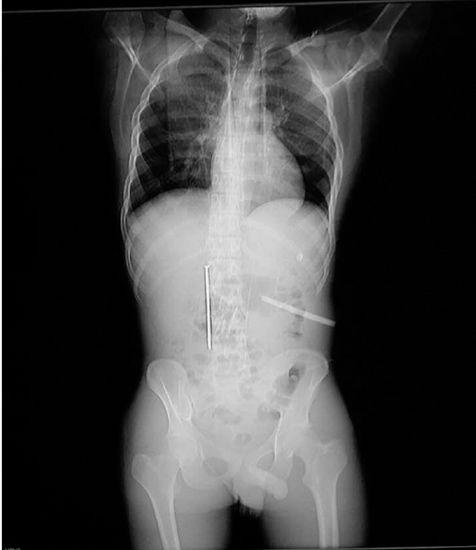

Nghĩ rằng đây là cách kiếm tiền dễ và đơn giản. Xiao Gong lập tức đi thách đố một người đàn ông lạ mặt để kiếm tiền. Anh ta thách người đàn ông nuốt đinh dài 13cm, đường kính 6mm, sẽ được 2000 tệ (khoảng 7 triệu đồng), nếu nuốt lưỡi cưa dài 12cm, rộng bằng ngón tay trỏ sẽ được 4000 tệ (khoảng 14 triệu đồng).

Xiao Gong đã không quan tâm đến tính mạng mà nuốt cả hai gồm một lưỡi dao răng cưa và một cây đinh dài gần 13cm để lĩnh số tiền trên. Tuy nhiên, ngay sau khi nhận tiền, Xiao Gong đã phải nhập viện vì bị đinh đâm thủng dạ dày. Còn chiếc cưa bị hoen rỉ đã khiến anh bị nhiễm trùng ổ bụng nặng.